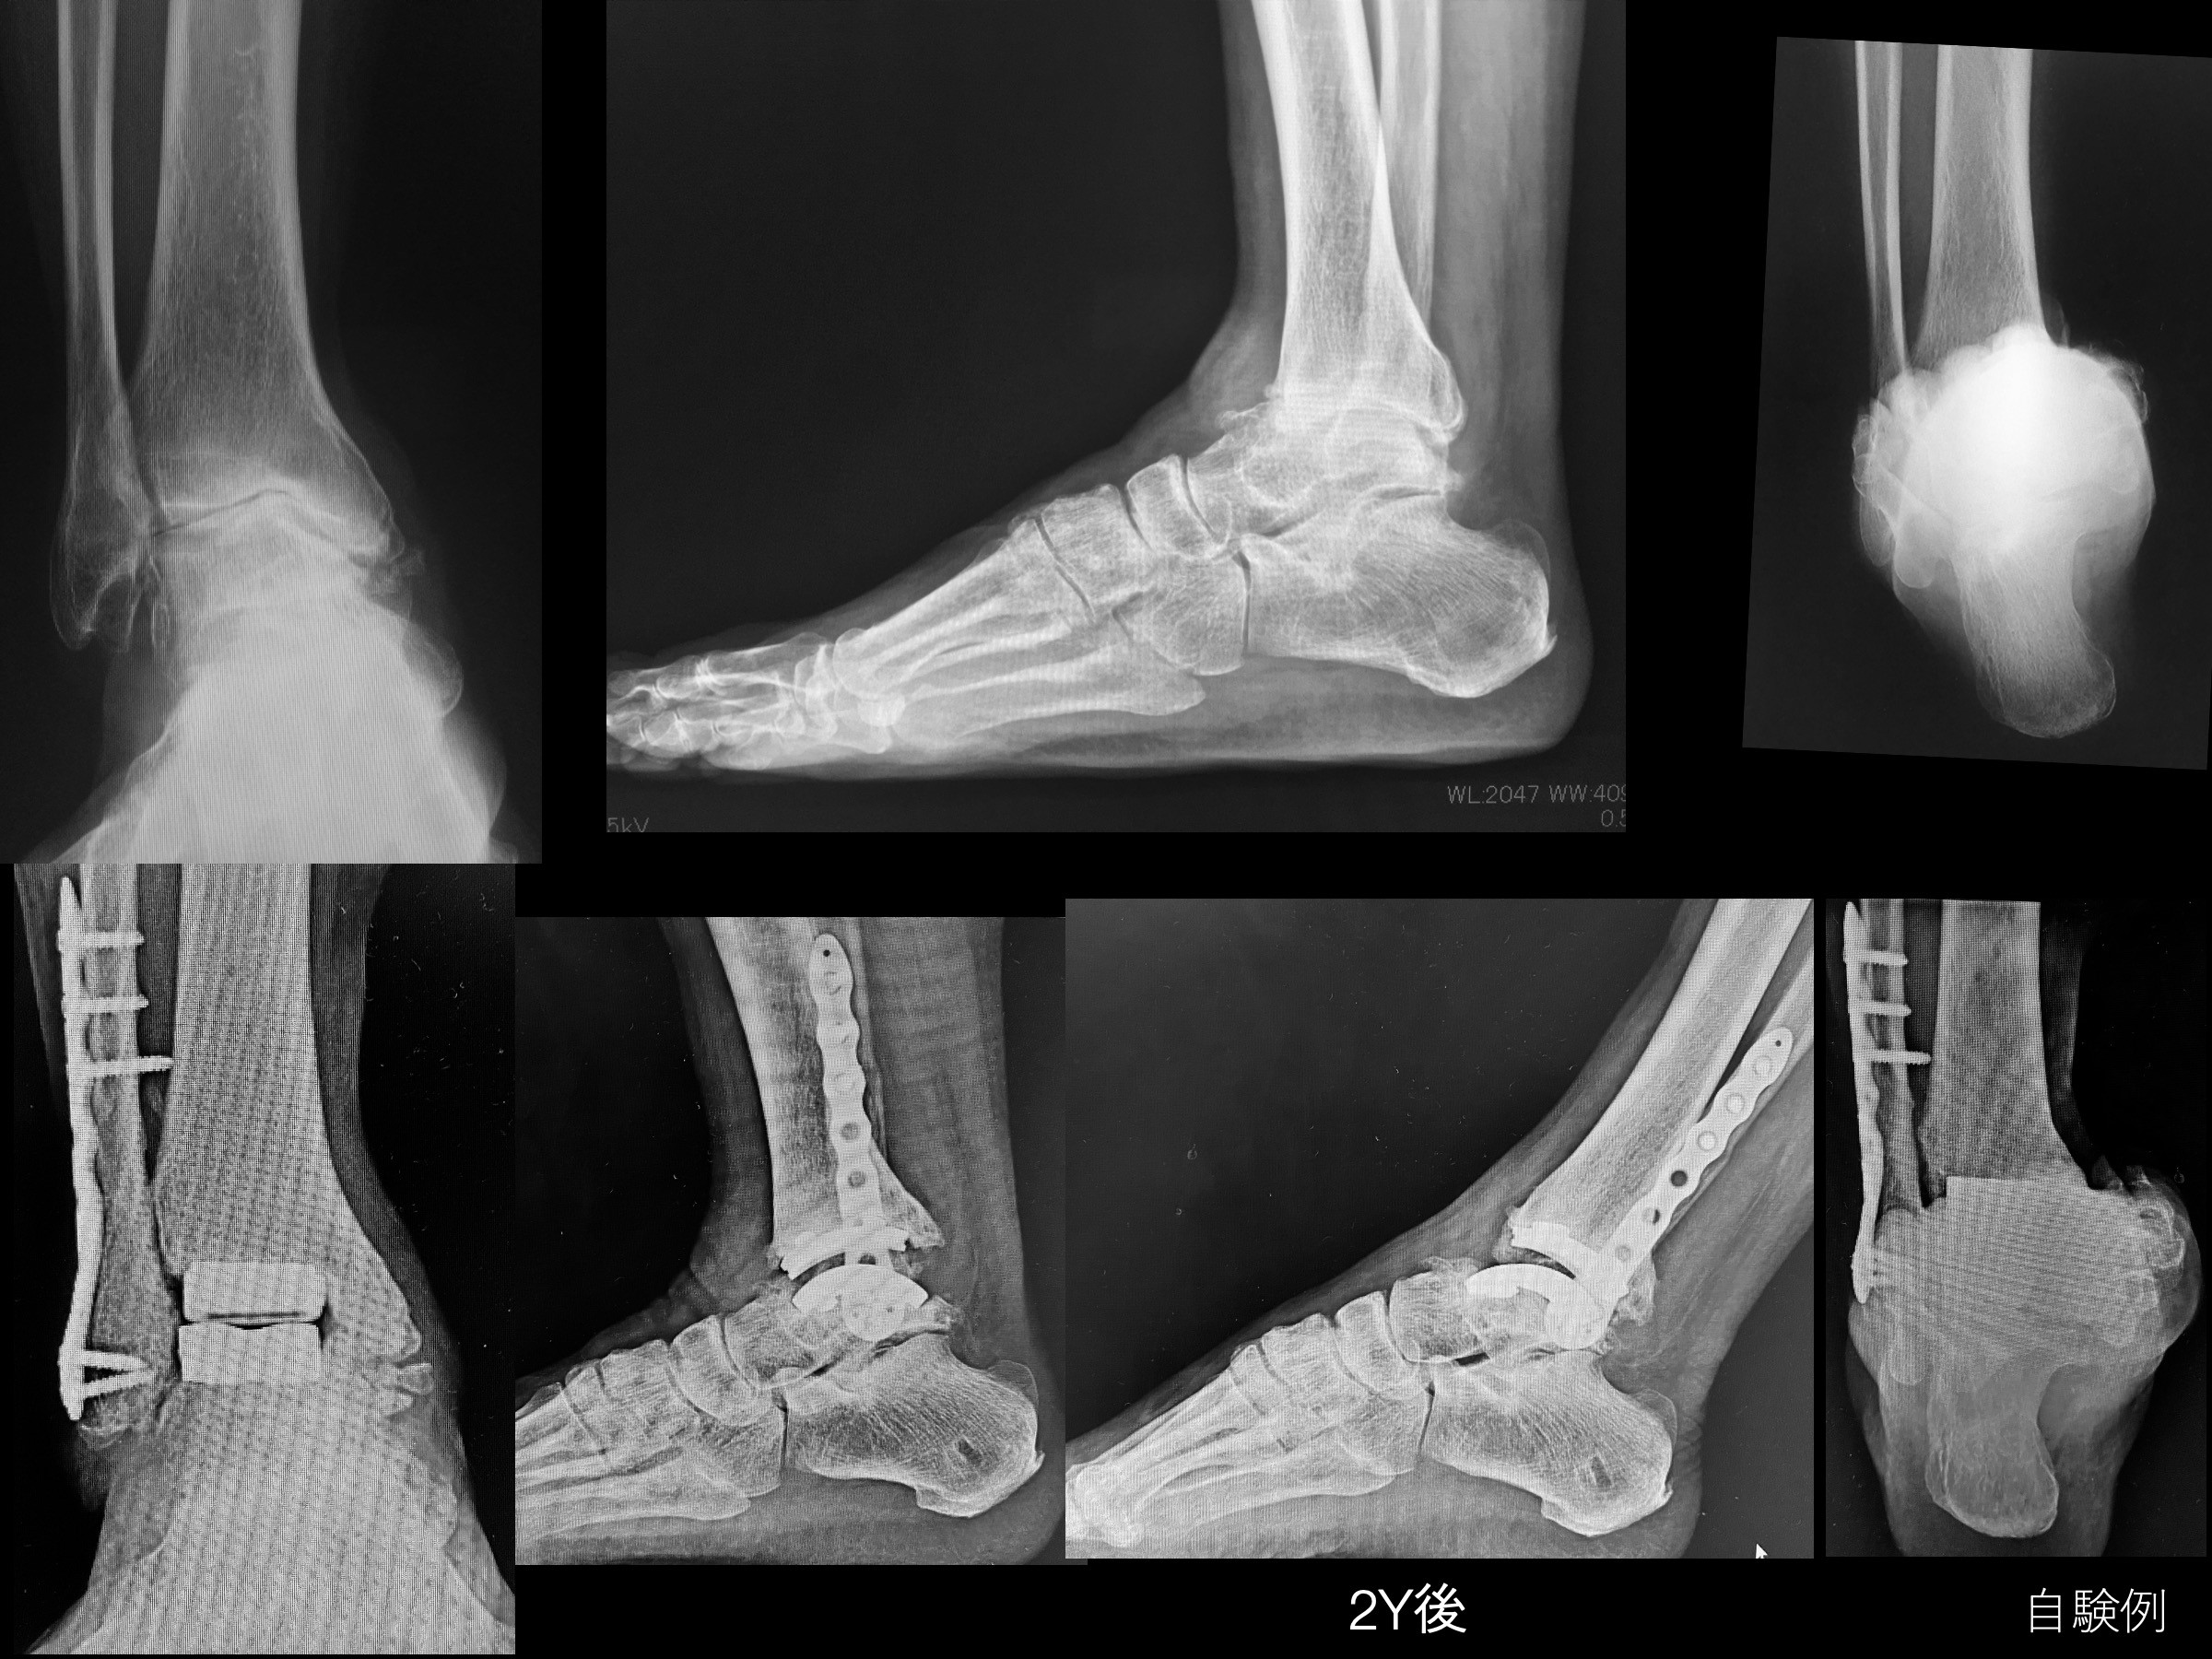

足部・足関節の手術 メジカルビュー社|整形外科|OS NEXUS 8 スポーツ復帰のための手術

「足部・足関節の手術」松田 秀一定価: ¥ 12000#松田秀一 #松田_秀一 #本 #自然/医療・薬学・健康裁断済みです。新品を業者にお願いしたので、書き込みもなく綺麗なままです。